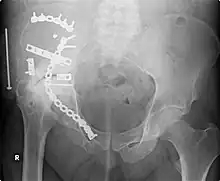

Orthopedic surgery or orthopedics (alternatively spelt orthopaedics) is the branch of surgery concerned with conditions involving the musculoskeletal system.[1] Orthopedic surgeons use both surgical and nonsurgical means to treat musculoskeletal trauma, spine diseases, sports injuries, degenerative diseases, infections, tumors, and congenital disorders.